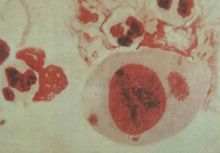

hogranvlo-ma,virus,PLV)、鸚鵝熱病毒群(Psittacosisvirusgroup)等,相當混亂。已按伯傑式分類法歸為衣原體目(Chlamidiales,L.A.Pagei等,1971)。然而尚有許多不明之處。侵染粒子呈直徑0.3微米的球形,可用光學顯微鏡看到;在被細胞壁和細胞膜包裹的細胞質中有核糖體;核酸同時含有DNA和RNA;已證明有葡萄糖代謝活性和蛋白質合成能力;在細胞液胞內增殖,不進入細胞質質內。侵染粒子通過吞噬作用進入細胞波胞內,轉化成一般稱為網狀結構體的粒子。網狀結構體通過分裂增殖,在浸染後期成熟為侵染粒子。因此,在增殖周期中,雖沒有保持作為粒子的連續性的潛伏期,然而,由於沒有證實網狀結構體的侵染性,所以從外表看起來,有一個相當於潛伏期的時期。為此,如上所述,微生物。衣原體與細菌的主要區別是其缺乏合成生物能量來源的ATP酶,也就是說衣原體自己不能合成生物能量物質ATP,其能量完全依賴被感染的宿主細胞提供。並以二分裂方式進行增殖,能被抗生素抑制。衣原體屬於原核類生物。圖片說明:Giemsa染色,油鏡(1000倍),見到一大單核細胞,包漿內有球形和橢圓形的包涵體。

衣原體在宿住主細胞內繁殖有特殊生活周期,可觀察到兩種不同的顆粒結構:(1)原體(elementarybody,EB)直徑為0.2~0.4μm的小球形顆粒,有胞壁,內有核質和核蛋白體,是發育成熟的衣原體,為細胞外形式。Giemsa染色呈紫色,Gimenez染色呈紅色。原體具有高度的感染性,在宿主細胞外較穩定,無繁殖能力,通過吞飲作用進入胞內,原體在空泡中逐漸發育、增大成為網狀體。(2)網狀體(reticulatebody,RB)或稱始體(initialbody),EB通過吞飲作用進入胞內,由宿主細胞包圍EB形成空泡,並在空泡內逐漸增大為RB。直徑為0.5~1.0μm,圓形或橢圓形。電子緻密度較低,無胞壁,代謝活潑,以二分裂方式繁殖。RB為細胞內形式,無感染性,Macchiavello染色呈藍色。RB在空泡內發育成許多子代EB也稱為包涵體。成熟的EB從宿主細胞中釋放,在感染新的易感細胞,開始新的發育周期,整個發育周期約需48~72h.